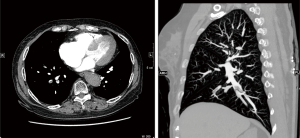

Next, the abdominal CT revealed that the transverse colon and colonic hepatic curvature were thickened and densified, the serous membrane surface was rough, and the fat exudation had improved. Subsequently, pulmonary artery computed tomography angiography (CTA) was performed, which suggested (Figure 4) multiple filling defects at the distal end of the right pulmonary artery, the distal end of the right upper pulmonary artery, the proximal end of each segment of the arteries, the dorsal segment of the right lower lung, the proximal branch of the basal segment of the artery, and the distal end of the left lower lobe of the basal segment. Thus, a diagnosis of pulmonary embolism was considered. Additionally, the thrombotic thrombocytopenic purpura (TTP) test results were negative.

On August 3, 2021, the patient returned to visit the Hematology Department. The patient had no abdominal pain, diarrhea, or hematochezia, and no significant change in body weight. Her laboratory test results were as follows: WBC count: 11.64×109/L, Hb: 118 g/L; platelet count: 11×109/L; serum potassium: 3.38 mmol/L, and D-dimer: 280.00 ng/mL. Her liver and kidney function indexes were normal. Reexamination of pulmonary CTA suggested that the absorption of the pulmonary embolism had largely improved (see Figure 5). In November 2021, another colonoscopy was performed, which showed no obvious abnormalities in the whole colon.